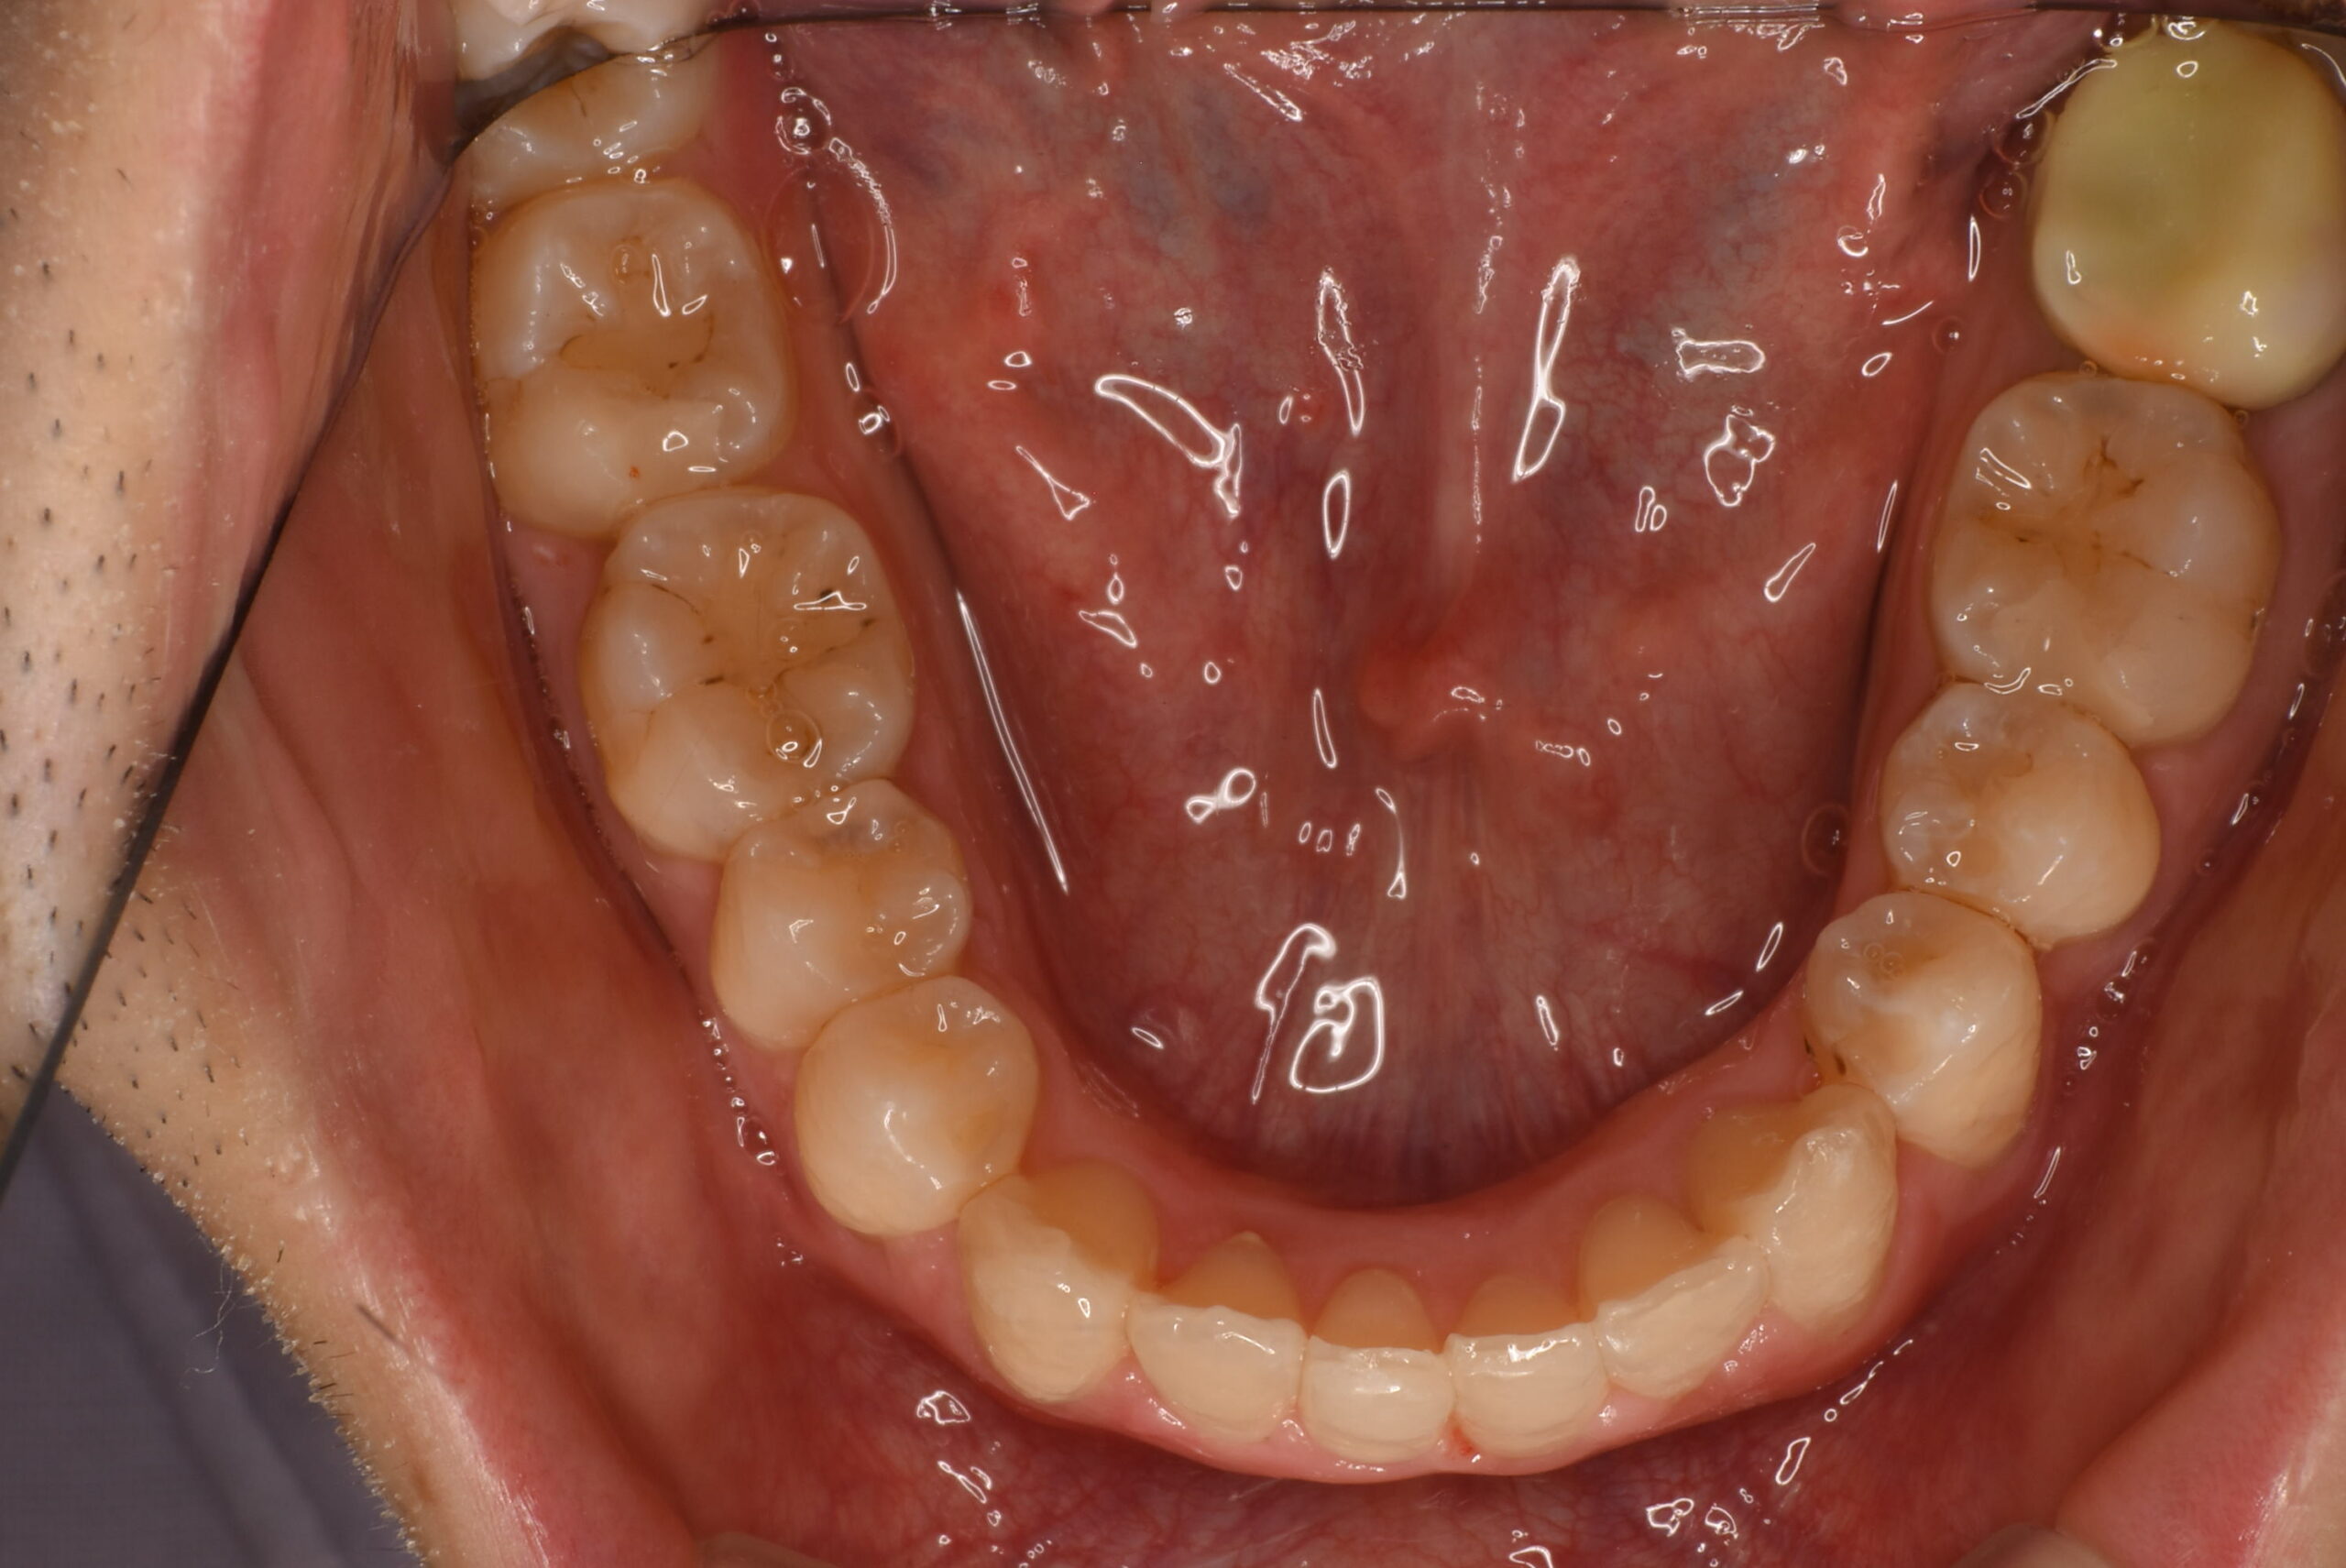

- AFTER

治療後_下顎咬合面